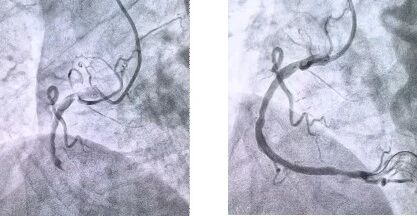

者抵達(dá)醫(yī)院后,簡(jiǎn)化掛號(hào)、繳費(fèi)等中間環(huán)節(jié),迅速溝通病情,需要緊急介入治療,獲得家屬同意,立即送至導(dǎo)管室。造影顯示其右冠狀動(dòng)脈中段完全閉塞,醫(yī)生迅速實(shí)施血栓抽吸,球囊擴(kuò)張和藥物洗脫支架植入術(shù)。36 分鐘后,閉塞血管恢復(fù)正常血流,吳大爺?shù)难獕骸⑿穆手饾u平穩(wěn),胸痛癥狀明顯緩解。術(shù)后三天,他便轉(zhuǎn)入普通病房進(jìn)行康復(fù)訓(xùn)練,重拾健康生活。